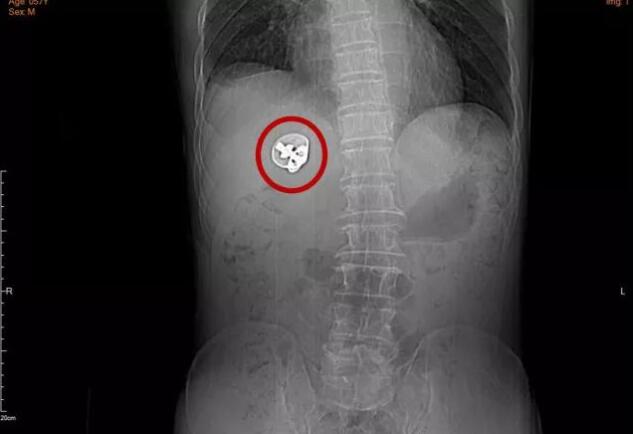

▲患者腹部CT平扫

肝胆外科主任医师陈拥军接诊后,安排黄先生完善了相关检查后,紧急联系放射科专家对他的影像学资料进行讨论。他们发现,患者右肝后有一个直径约三厘米的金属异物,异物前方形成了七厘米左右的脓肿,并在周围引起慢性炎症,右侧腹壁皮下水肿积液,两下肺慢性炎症。